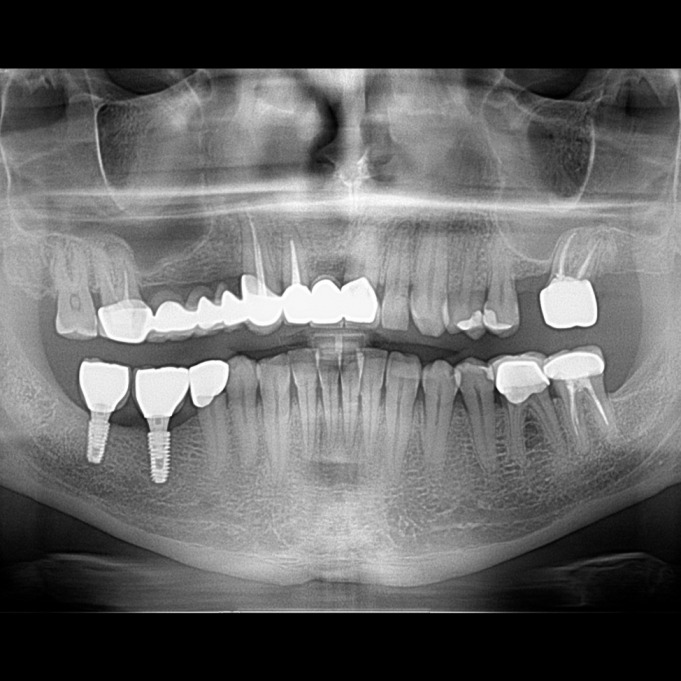

İmplant etrafındaki kemik açıklığını kemik grefti ile tedavi ettiğimiz vakamızdan biri